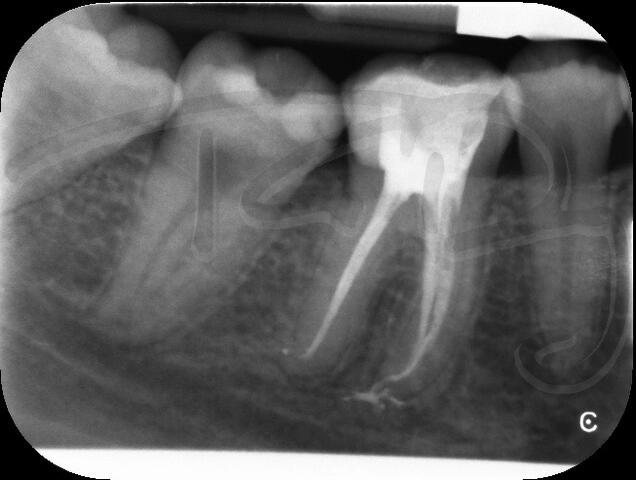

I am pleased to take endodontic referrals. Curved canals >30 degrees and potentially greater than 50 degrees can be negotiated. Sclerosed canals accessed. Post spaces prepared and the patient returned to you ready to restore.In most cases existing crowns, bridges and veneers can be retained with the endodontic access aesthetically restored after the full canal network has been treated.In the first instance I would prefer a radiograph and a brief list of patient expectations and a tooth history.

I really enjoy undertaking root canal treatments - rising to the challenge and helping people out of dental pain for the long term.I was privileged to be asked to speak at the 2016 BDA Conference, where I have a lecture about providing quality endodontic outcomes to patients, working as a generalist. Avoiding problems and pitfalls and maximising efficiency. One of the main matters that he covered was understanding that what is seen on plane radiography is utterly misleading and should not be the criteria by which a generalist continues treatment once it has been started.

At the 2016 BDA Conference, Thomas spoke about providing quality endodontic outcomes to patients, working as a generalist. Avoiding problems and pitfalls and maximising efficiency. One of the main matters that he covered was understanding that what is seen on plane radiography is utterly misleading and should not be the criteria by which a generalist continues treatment once it has been

started.